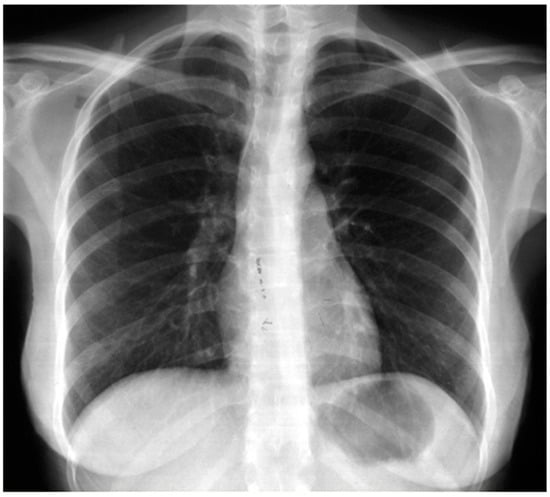

| Bilateral Pneumothorax | 1 | 1.72 |